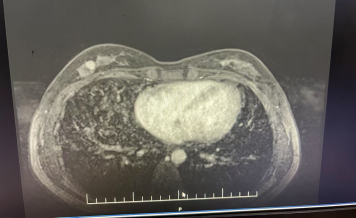

·精准评估:超声检查提示「4a 类结节」,经穿刺活检确诊为早期浸润性癌。

·个性化治疗:陈雷医生团队结合她的年龄、肿瘤大小及位置,决定采用保乳保腋手术,确保切缘干净,同时保留乳房形态。